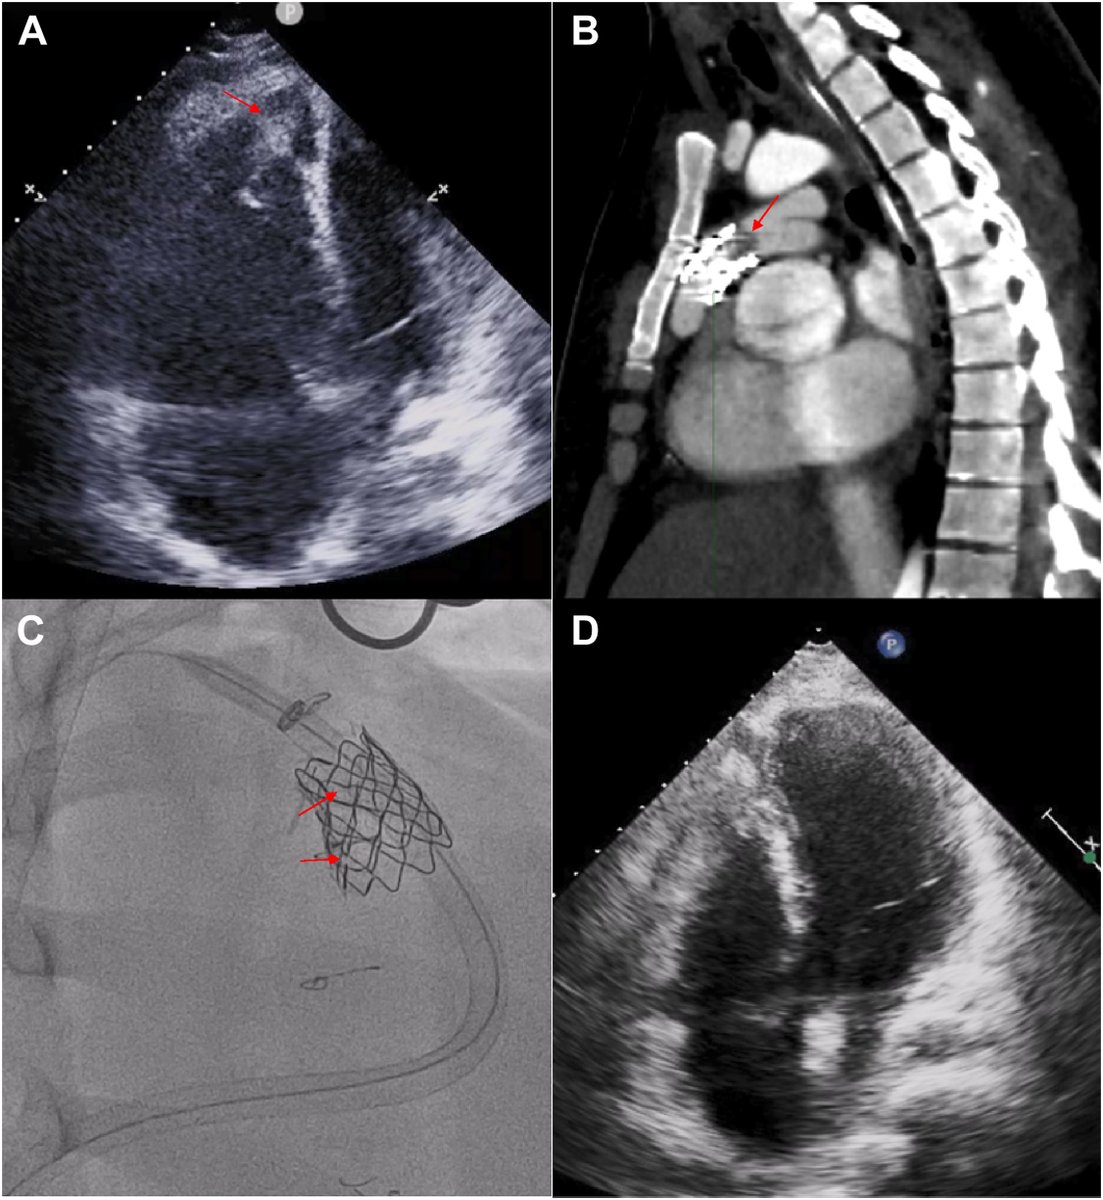

Decanulación percutánea con dispositivo Manta del oxigenador extracorpóreo de membrana venoarterial periférico. #RECintervcardiol #AheadOfPrint Emilio Arbas Redondo Clara Ugueto J. Caro Alfonso Jurado-Román Raul Moreno 🔗recintervcardiol.org/es/cartas-cien…

♦️Ya está disponible en #recintervcardiol nuestra experiencia en el uso del Manta para la decanulación arterial en pacientes con asistencias mecánicas circulatorias periféricas como el ECMO-VA. Cardiología La Paz REC Publications #aheadofprint recintervcardiol.org/es/cartas-cien…